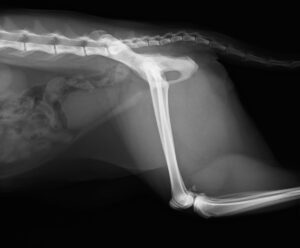

【整形外科】 右大腿骨頭すべり症

ジャンプした拍子に右後肢跛行とのことでかかりつけ医を受診後、セカンドオピニオンとして当院の整形外科に来院されました。若い雄猫に多く見られる「大腿骨頭すべり症」と診断。ご家族様と相談の上、骨頭切除を実施しました。経過は順調でしたが、その6ヶ月後に逆側も同様に骨折し、同治療を行いました。結果的に両側の骨頭切除が行われましたが、経過は良好です。